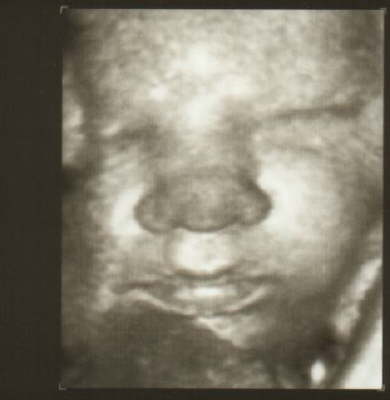

Erst am Montag sollte eine Untersuchung alles aufklären. Zur Ablenkung machte man dann noch einen 3D Ultraschall, damit wir unseren Sohn schon mal betrachten konnten. So sieht unser kleiner also aus:

Das St. Anna in Duisburg ist eines der wenigen Krankenhäuser die vor einer Entbindung einen solchen Ultraschall durchführen. Dieser wird, so Dr. Kucharsky, nicht in Rechnung gestellt und ist eine Serviceleistung die unserem Sohn das Leben gerettet hat. Wir würden uns wünschen, dass alle so handeln.